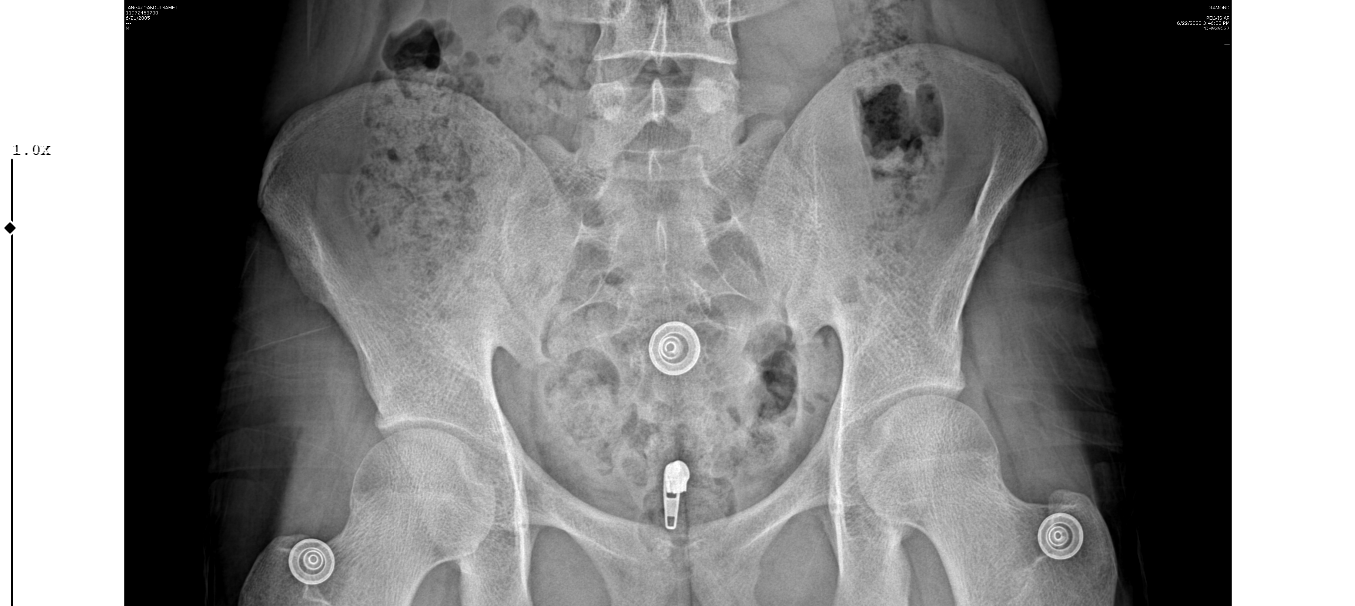

Konuyu hortlatıyorum ama hocam benim röntgeni de yorumlar mısınız acaba? 18 yaşına yeni girdim plaklar kapalı mı açık mı?

hayır

Foto gayet netti, parmaklarınızdaki plaklar kapanmış, ulna başındaki kapanmış ya da kapanmak üzere, sadece radius başındaki kalmış. Bu da yaklaşık 17-18 kemik yaşı arası bir yere denk geliyor benim ders notlarıma göre. Bize fakültede öğretilen de "Kemik yaşı 16 olmuş ve kişi son 1-2 yılda hiç uzamamışsa, erişkin boyuna ulaşmış demektir". Eğer son yıllarda biraz uzadıysanız, bir iki yıl daha birkaç cm uzarsınız ama kemik yaşınız hakkında yanılmıyorsam öyle ciddi bir boy atma dönemi beklememelisiniz. Üzülecek bir şey yok, boydan çok daha önemli şeyler var hayatta. Kişiliğiniz, kilonuz, vücudunuza, giyiminize gösterdiğiniz özen, iyi arkadaşlara sahip olmak, mesleğiniz vs.

Endokrin doktorunuza tekrar gittiğinizde daha düzgün bilgilendirirler, onların uzmanlık alanı ve her gün gördüğü işi bu. Ben sadece fakültede 3 yıl önce 2-3 saat ders olarak işledim, biraz da kendi imkanlarımla Çocuk Sağlığı ve Hastalıkları kitapları okudum o kadar, yanlış veya eksik biliyor olmam olası.

16 kemik yaşından sonra uzama olabiliyor son 1 yılda <1 cm uzamışsa erişkin boyu kabul ediliyor